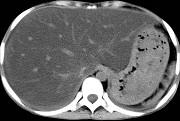

问题 男,57岁,肥胖、糖尿病、血脂升高,CT扫描如下图,请问诊断或描述错误的是哪一项 ( )

选项 A、密度均匀减低 B、血管影清唽可见 C、脂肪肝 D、肝脏增大 E、肝硬化

答案 E